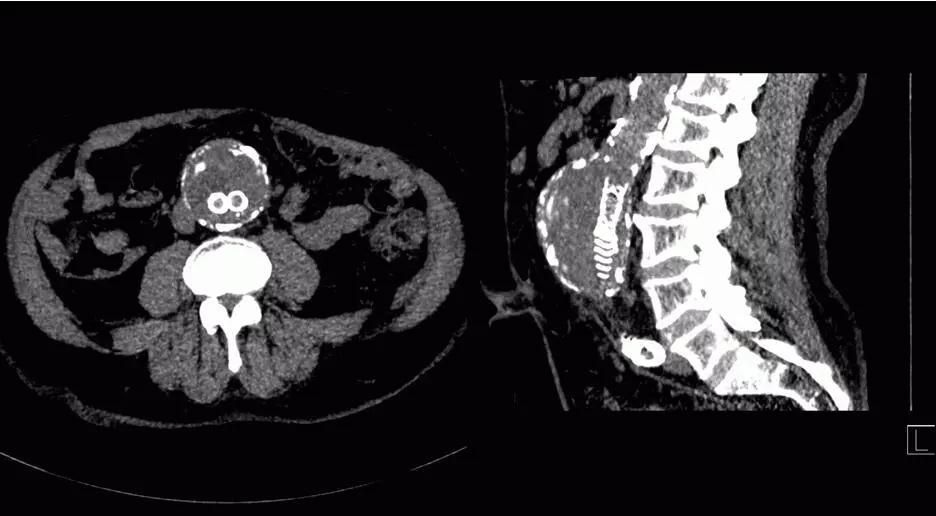

Force CT突破了探測器的限制,實現(xiàn)業(yè)內(nèi)最寬的80cm大范圍、5倍于寬體CT探測器覆蓋范圍,真正實現(xiàn)全臟器灌注,同時具備低70KV灌注成像技術(shù),可以做到全器管灌注的輻射劑量只相當(dāng)于一次CT平掃。

而其他廠商生產(chǎn)的寬體CT的最寬覆蓋范圍只有16cm,全身除心臟之外器官都超過16cm,因此16cm不夠?qū)?,同時寬體探測器固有的弊端——“錐形束”偽影一直沒有得到有效解決。

△70 kV胰腺神經(jīng)內(nèi)分泌腫瘤灌注

6.低劑量全臟器灌注和動態(tài)血流成像:

超大范圍80厘米功能成像,只需要一次平掃的輻射劑量,既可完成一站式全器官灌注掃描(神經(jīng)、體部、心?。┖蛣討B(tài)血流評估,更安全而全面的獲取形態(tài)學(xué)和功能學(xué)信息。

△肝臟5D灌注,本底輻射劑量,取代傳統(tǒng)多期相掃描

SOMATOM Force 突破技術(shù)界限,將血流評估覆蓋范圍擴大至80cm,特別適合大范圍下肢血管疾病診斷,一次掃描一次注射即可無創(chuàng)精確判斷病變,更加精確地制定臨床決策,選擇合理的治療方法。

△80厘米無創(chuàng)CT DSA,影像決策診療